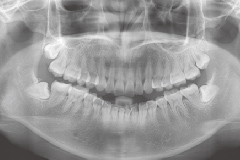

X片檢查

影像記錄